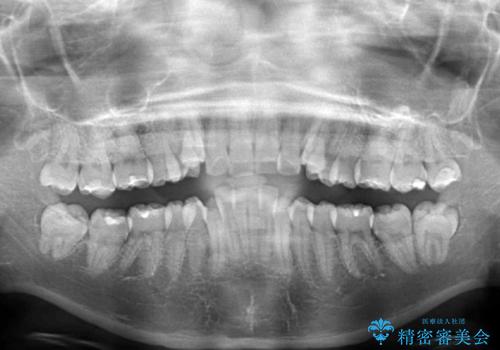

- 前歯のデコボコと上顎の前突感による口の閉じにくさを気にして来院された患者様です。

目立たない装置を希望されたので、上顎が裏側装置のハーフリンガルを選択し、上下左右の小臼歯(計4歯)を抜歯して矯正治療を行うこととしました。

治療期間の目安は2年半~3年間でしたが、咬み合わせにより上顎装置が頻繁に脱落してしまい、治療期間が長期化してしまいました。

期間はかかったものの、口元の張り出し感や歯のデコボコが解消され、患者様には大変満足していただけました。